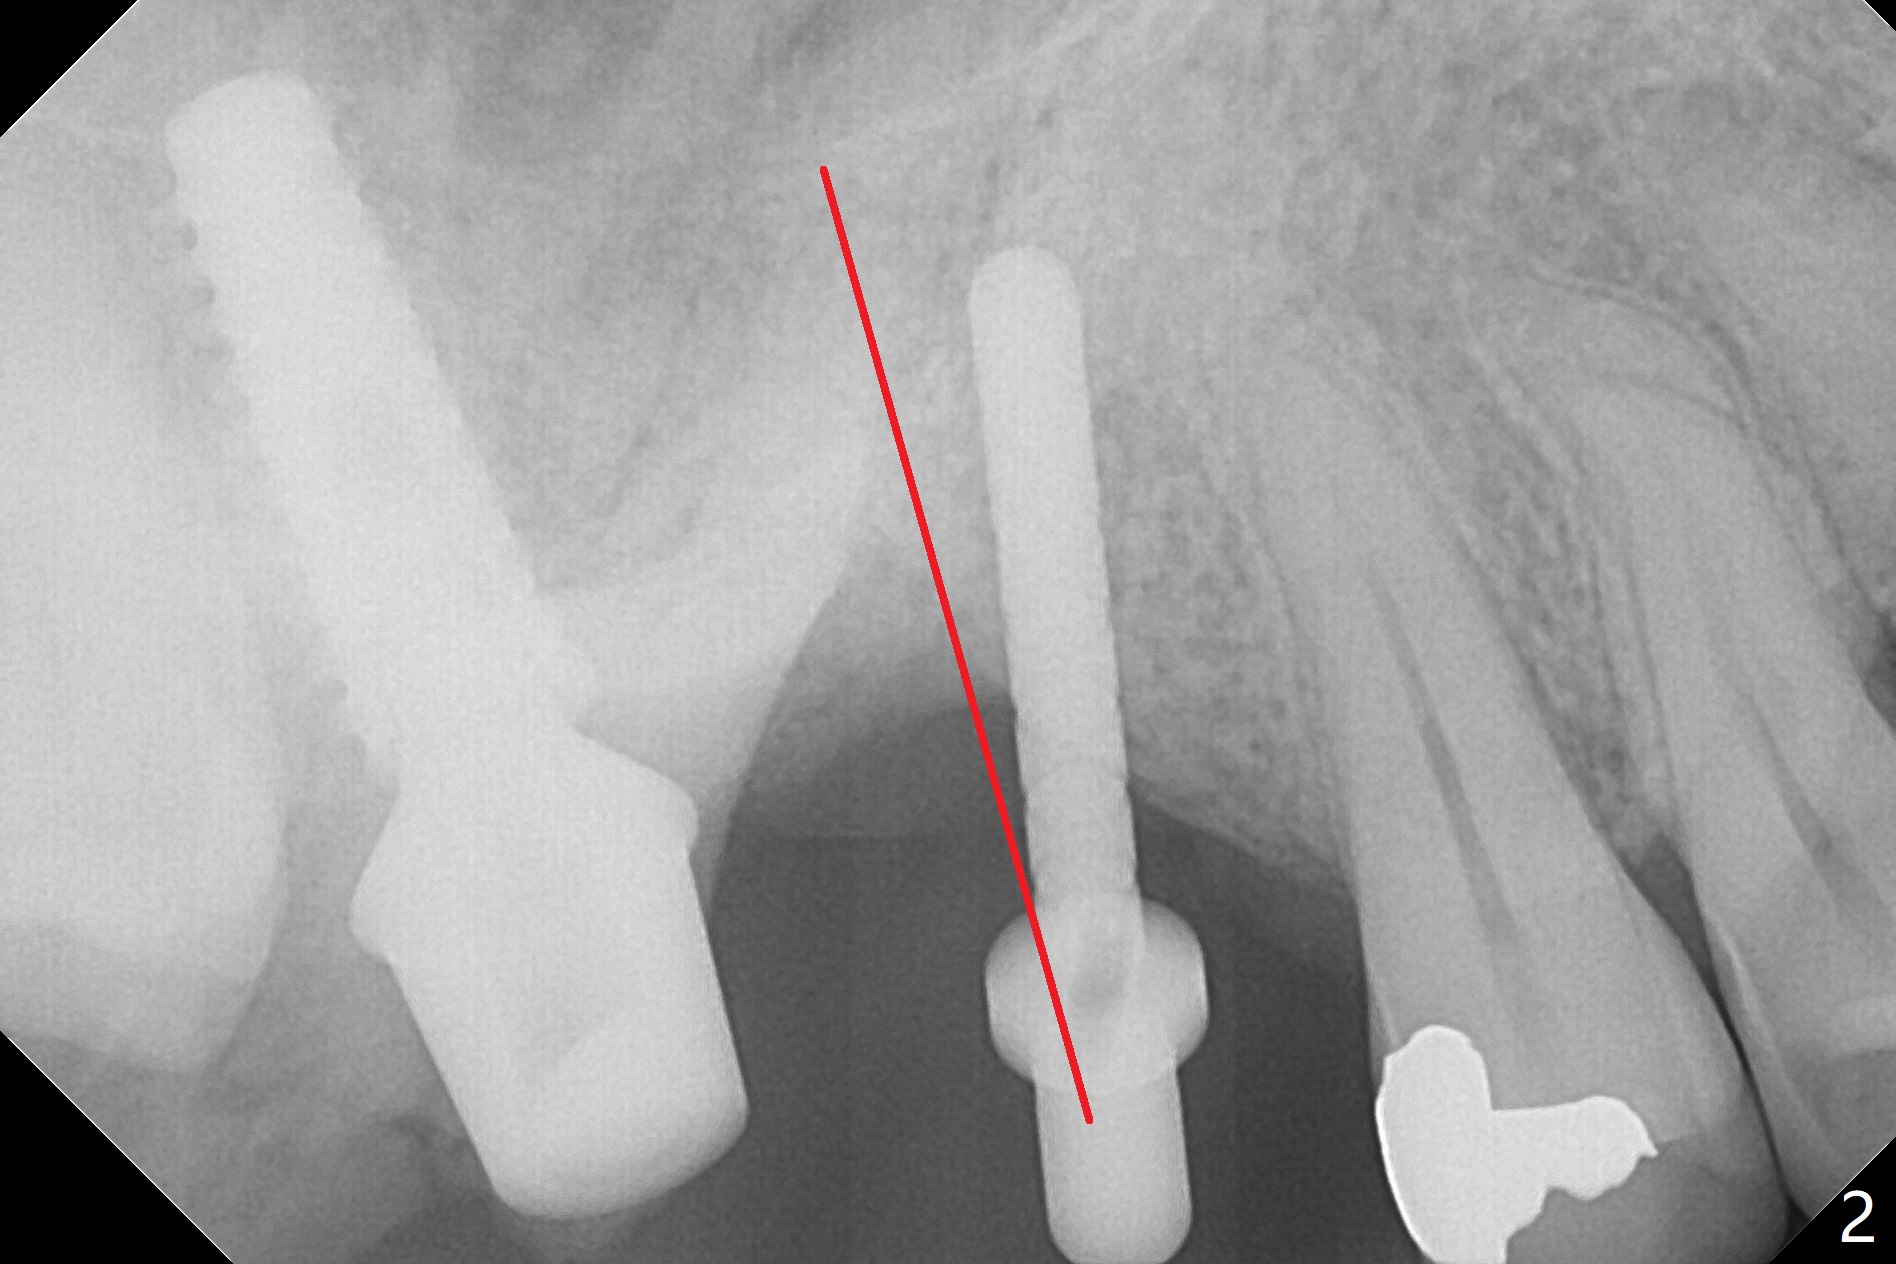

The gingiva at #2 adapts to the abutment 3.5 months post placement (Fig.1). After incision, osteotomy at #3 is initiated by free hand, which is found off (Fig.2 (red line: normal trajectory)). After repositioning osteotomy, a 4.5x11 mm dummy implant is placed with minor trajectory issue (Fig.3). Following further adjustment, a 5x11 mm implant is placed with relatively normal axis; a 6.5x4(4) mm abutment is inserted. Autogenous bone, Vanilla and Osteogen are placed distobuccally (Fig.4). Guided surgery should be more efficient and precise. There is no implant thread exposure 9 and 5 months postop at #2 and 3, respectively (Fig.5,6). The mesial wall of the crown at #2 is thin, having a crack line. The crowns at #2 and 3 are cemented with RelyX Ultimate Adhesive Resin Cement bonding. If the crown fractures, change the abutment (6.5x5.7(2) mm) to the one with smaller diameter (4.5 or 5.0 mm), or trim the abutment mesially heavily. Guided surgery or stent should prevent the potential complication.